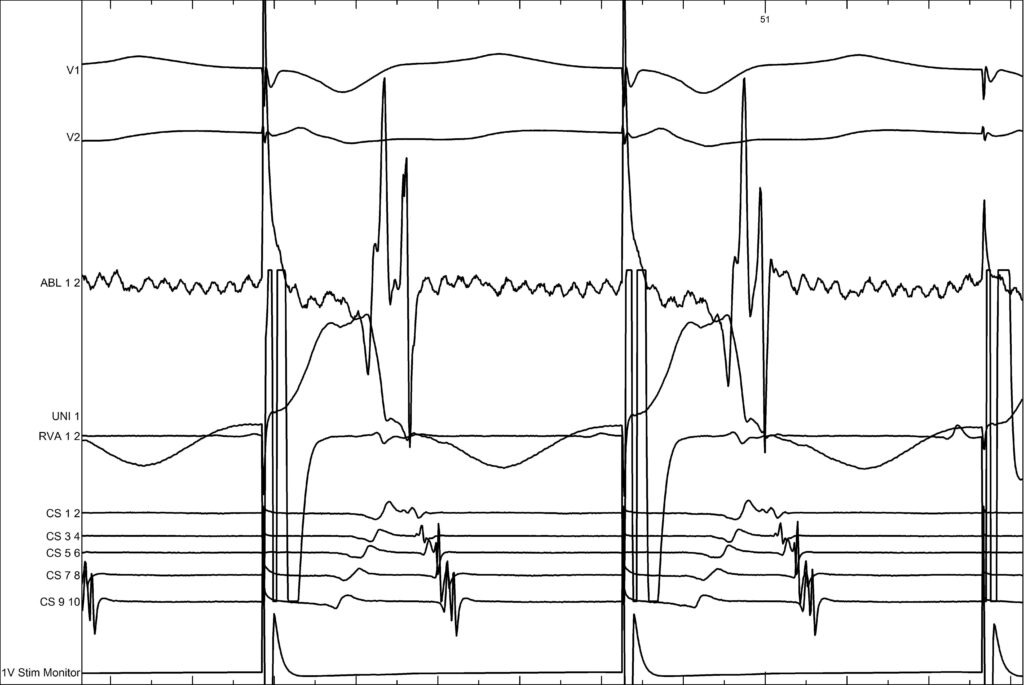

Now we inject adenosine to see whether there is any conduction through the accessory pathway. You can clearly see that after the adenosine injection, the activation remains concentric with block, which confirms that there is no longer any conduction through the accessory pathway